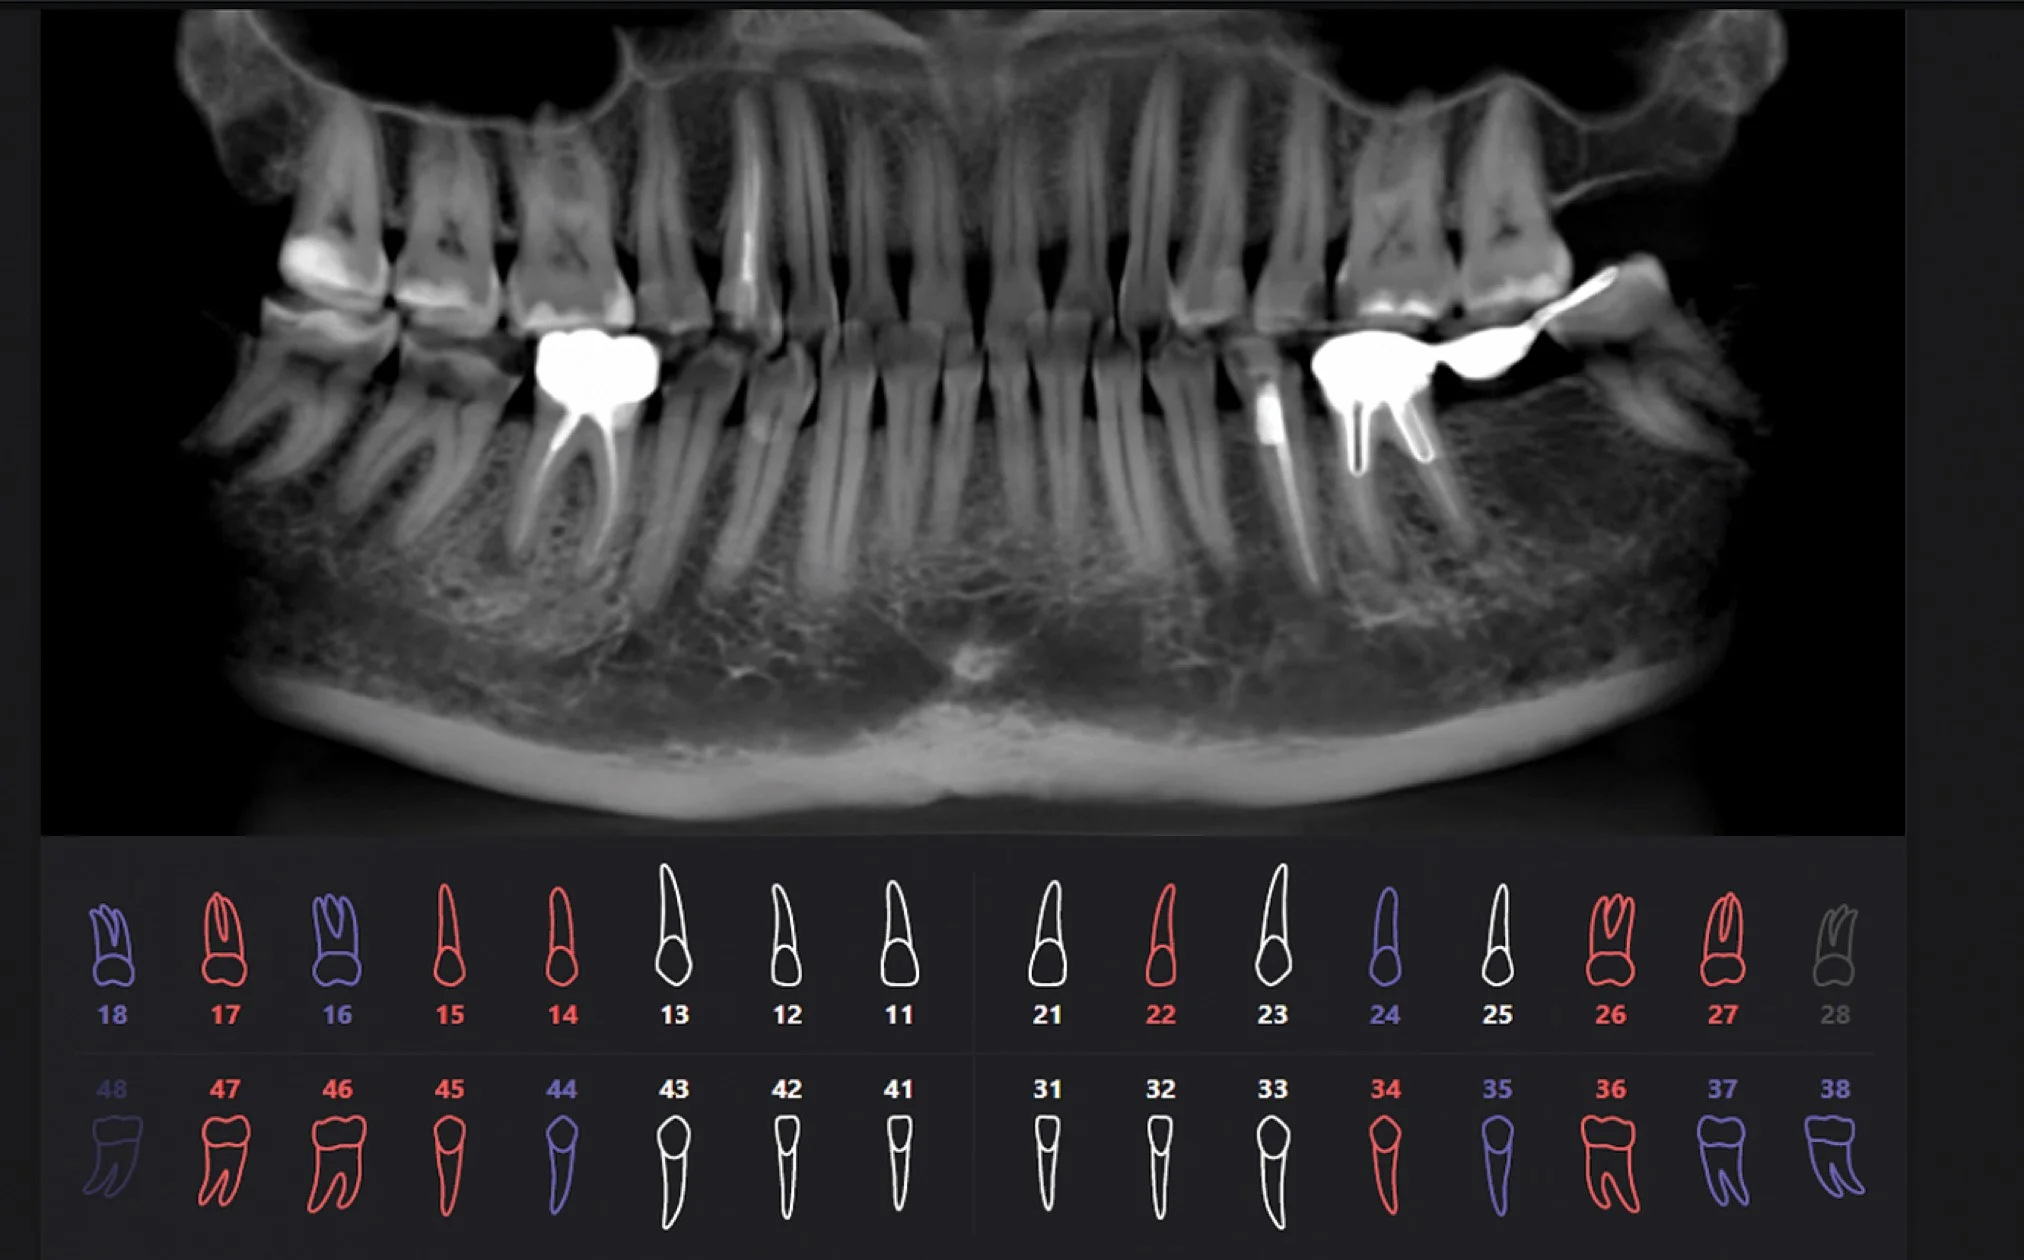

Искусственный интеллект и 3D снимки

3D снимки — это новый уровень диагностики. Но при их появлении возникла достаточно большая сложность.

Дело в том, что 3D снимки гораздо более информативны, чем 2D снимки, но на их чтение требуется гораздо больше времени и более высокая квалификация стоматолога, это гораздо более трудоемкий процесс.

Далеко не каждый стоматолог, умеет правильно читать КТ снимки, для этого требуется отдельное обучение. Также стоматологам не хватало времени выделяемого на прием, чтобы проанализировать каждый зуб.

Что привело к тому, что комплексность диагностики начала страдать. Врачи успевали проанализировать только 1-2 зуба за прием.

Для решения этих проблем была создана Российская разработка, работающая на основе искусственного интеллекта.

- Программа ежедневно собирает данные 3D снимков со всей России и совершенствуется в их чтении;

- На данный момент было изучено более 60 000 КТ снимков;

- Программа разрабатывается с участием ведущих мировых экспертов челюстно-лицевых рентгенологов и стоматологов.

Результат работы искусственного интеллекта

Красным цветом показаны проблемные зубы, синим цветом — зубы с пломбами или ортопедическими конструкциями, белым цветом — здоровые зубы.

Сравнение подходов в изучении 3D снимков

Когда мнение врача и искусственного интеллекта отличается

Мнение врача и искусственного интеллекта иногда может отличаться, это сигнал для того, чтобы более глубокого изучить проблемную область, назначить ремтерапию, динамическое наблюдение.

Определяющее мнение всегда остается за врачом.